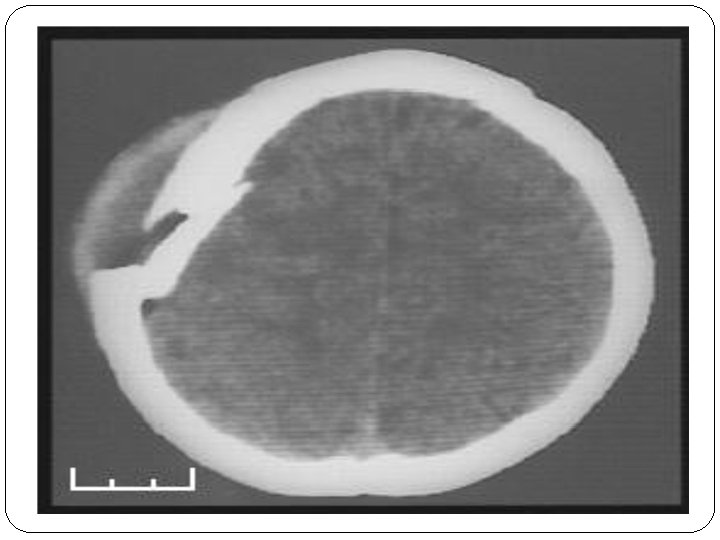

3 - PHYSIOPATHOLOGIE Les lésions peuvent être classées en lésions primaires et secondaires : Ø LES LÉSIONS PRIMAIRES inhérentes au traumatisme lui-même comprennent : * Les fractures du crâne * Les hématomes extra cérébraux, HSA * Les lésions intra parenchymateuses (contusions, lésions axonales diffuses). Ø LES LÉSIONS SECONDAIRES souvent plus dévastatrices que les atteintes primaires : * Engagements cérébraux et leurs complications vasculaires. * Œdème cérébral.

5 - INDICATIONS NEUROCHIRURGICALES À LA PHASE PRÉCOCE Il existe un consensus pour les indications de la chirurgie extra-parenchymateuse. Ces indications sont : – l’évacuation la plus précoce possible d’un hématome extradural symptomatique quelle que soit sa localisation. – l’évacuation d’un hématome sous-dural aigu significatif (épaisseur supérieure à 5 mm avec déplacement de la ligne médiane supérieur à 5 mm); – le drainage d’une hydrocéphalie aiguë; – le parage et la fermeture immédiate des embarrures ouvertes; – la réduction d’une embarrure fermée compressive